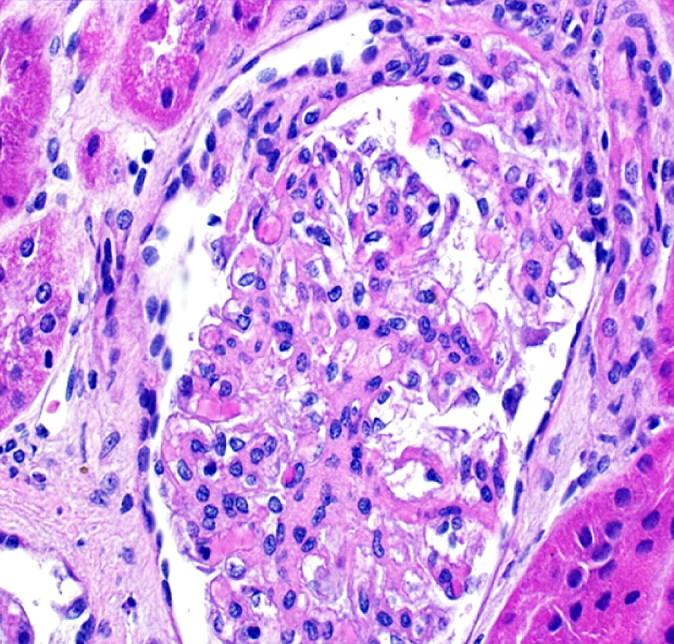

Falling through the cracks of vasculitis classification-a report of three patients.

NDT Plus. 2011 Oct;4(5):327-30. doi: 10.1093/ndtplus/sfr054. Epub 2011 Apr 14.